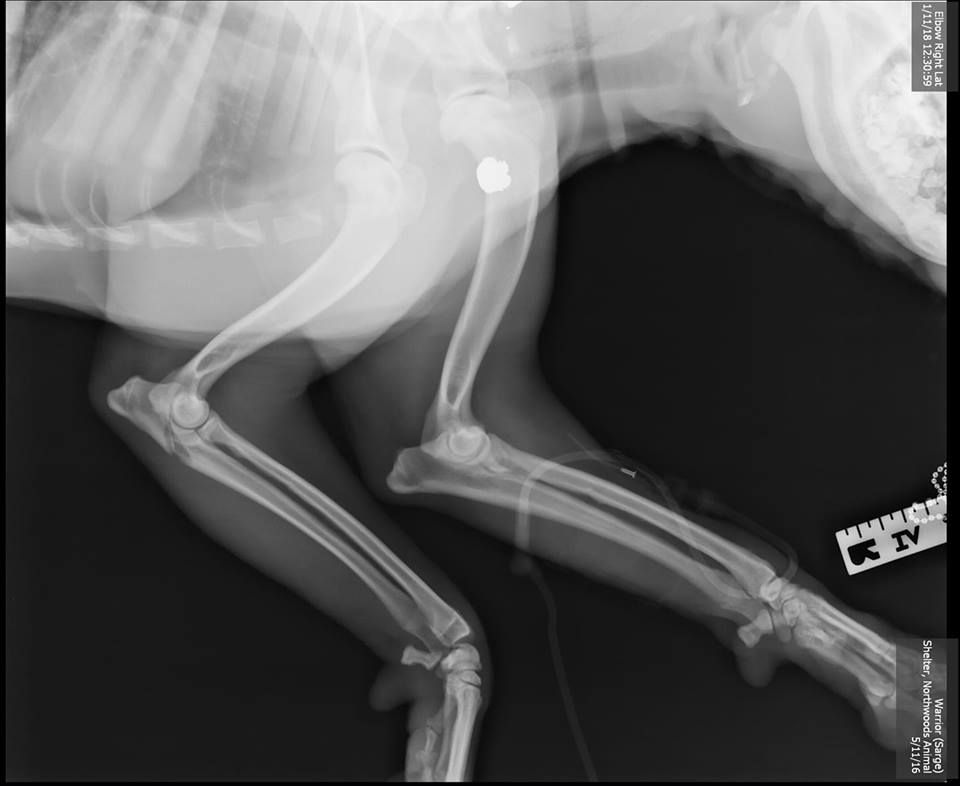

Following initial treatment by Four Seasons Animal Hospital, also in Iron River, Sarge and Erickson made the more than four-hour drive to UW Veterinary Care for specialized surgery. A fracture to Sarge’s ulna (one of the two bones of the forearm) near the elbow required delicate repair, set with a bone plate and seven screws.

“It was difficult as it involved the elbow joint, so it was extremely important to anatomically reconstruct the pieces to prevent or minimize arthritis long-term,” explains Jason Bleedorn, a clinical associate professor of orthopedic surgery who led Sarge’s operation.

The team also removed the bullet that could have claimed Sarge’s life. X-rays revealed that the bullet entered Sarge’s skull near his right eye, tracked along the jaw, fractured parts of his neck vertebrae, then lodged near his shoulder. “The injuries from the bullet could have been much worse,” says Bleedorn. “He was very lucky.”